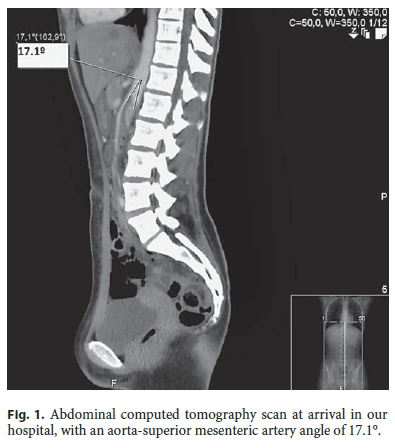

When observed at our hospital (hours later), she was not in acute distress, her body mass index was 17.9, and her vital signs were within the normal range. She had epigastric tenderness and hyperactive bowel sounds without palpable masses or organomegalies. The remaining examination was unremarkable. Complete blood count, serum electrolytes, urea, creatinine, and C-reactive protein were normal; aspartate aminotransferase, alanine aminotransferase, and γ-glutamyl transferase were slightly elevated (42 U/L, 62 U/L, and 58 U/L, respectively). An abdominal CT scan revealed an acute angle of 17.1° between the aorta and the superior mesenteric artery (Fig. 1), narrowing the third portion of the duodenum.These findings established the diagnosis of SMAS.

The diagnosis is made by radiologic, angiographic, ultrasonic, and endoscopic studies. Abdominal X-ray can only show gastric distension at best. The upper gastrointestinal series contrast study has been the standard diagnosis procedure for decades (showing dilated first and second portions of the duodenum with abrupt vertical obstruction of the third portion); it consists of antiperistaltic waves of contrast moving away from the obstruction, a 4- to 6-h delay in transit of contrast to the jejunum, with relief of the obstruction through postural changes. Measuring the aortomesenteric angle in the abdominal angio-CT of a patient with symptoms can be diagnostic. In our patient, the diagnosis was made by an angio-CT scan after a SMAS suspicion due to clinical signs and acute gastric distention [4] discovered in the abdominal ultrasonography. In fact, CT is the exam that diagnoses this condition in about 94% of cases nowadays [2].